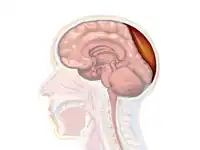

A diagram showing an epidural hematoma.